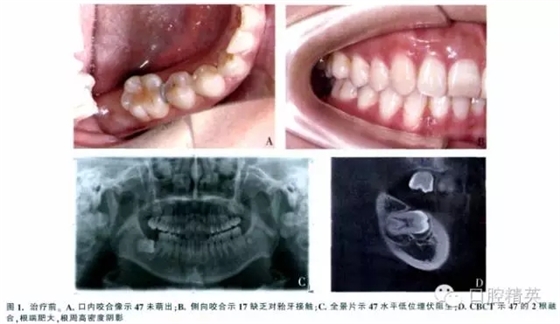

女,37歲,右下頜埋伏牙,要求治療。檢查示面型對稱,側貌正常。47未萌,17腭尖下垂,其余牙咬合好(圖1A、B)。全景片示:47水平低位埋伏,47冠方有一不完整的透明陰影,周圍呈現(xiàn)白色反應線,根方有致密陰影(圖1C)。錐形束CT(CBCT)示47接近水平位,牙長軸與牙合平面前上方夾角約為75°,根尖端肥大,牙周膜間隙模糊(圖1D)。